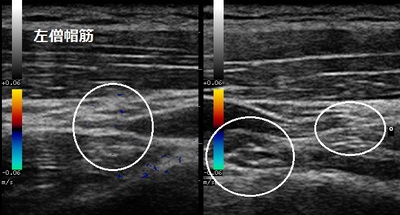

右肩(患部) 左肩(正常側)

右肩前方の上腕骨頭を押さえるととても痛みます。手のひらを下にして腕を挙げようとすると痛くて出来ません。超音波検査で棘上筋の一部が、正常側と比較して不整になり凹んで損傷していました(左画像の矢印)。凹んだ腱を修復させ、痛みを軽減させる理学療法を行います。

肩峰下インピンジメント症候群は、うでの上げ下ろしの時に棘上筋腱、棘下筋腱(腱板)が肩峰の下を通過します。肩峰と腱板の間には肩峰下滑液包があって、肩峰と腱板の摩擦や衝撃を和らげているが頻回の挙上動作により腱板や肩峰下滑液包の炎症を引き起こしたり、さらには腱板の断裂などの損傷を引き起こすことがあります。